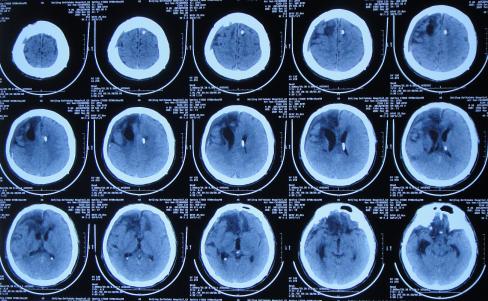

入院治疗5天即2021年1月1日,查头颅CT示脑积水和脑膨出均有减轻( 图-12 )。

图-12: 2021年1月1日头颅CT

入院治疗22天即2021年1月18日,查头颅CT示脑膨出变基本正常( 图-13 );脑脊液细菌已被消灭。

图-13: 2021年1月18日头颅CT